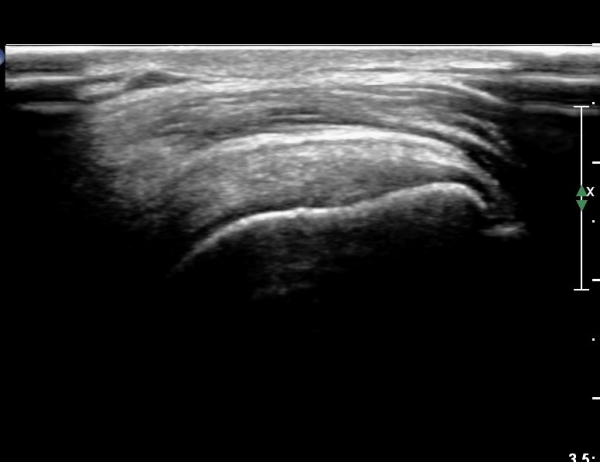

°ß°©ÇÏ±Ù°Ç ÇϺΠÁ¾´Ü¸é°Ë»ç¿Í Ⱦ´Ü¸é°Ë»ç °ß°©Çϱٰdz»  ¼®È¸È­ À½¿µÀÌ  °üÂûµÈ´Ù(»çÁø 3, 4).

°ß°©ÇÏ±Ù°Ç È¾´Ü¸é°Ë»ç»ó ¼Ò°áÀý ÇÊÁú°ñº¯È­¿Í °ß°©ÇÏ±Ù°Ç Áߺο¡ °í¿¡ÄÚ µ¢¾î¸®°¡ °üÂûµÇ°í

¼®È¸ À§ÂÊ(¸Ó¸®ÂÊ)ÀÇ ÈûÁÙÀÇ Àú¿¡ÄÚ º¯È­°¡ °üÂûµÈ´Ù(»çÁø 4, 5).